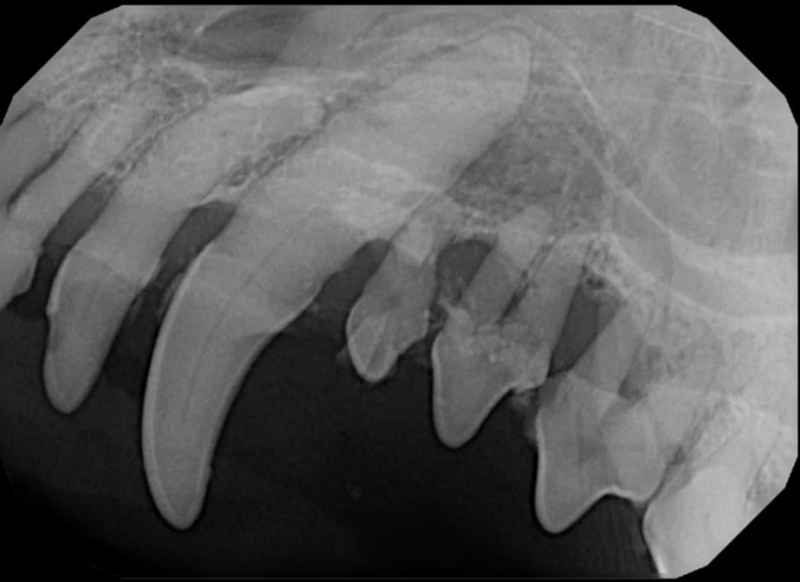

Surgical Extraction of Diseased Teeth

Periodontal disease is extremely common in dogs and cats. Over 80% of dogs and cats over two years of age have some degree of periodontal disease. Periodontal disease is best prevented by yearly professional dental cleanings starting at two years of age and at home brushing at least three times weekly. Brushing should begin at a very early age to allow your new pet to get used to regular brushing. In severe cases of infection or periodontal disease, the teeth may need to be surgically extracted. Extractions should always involve x-rays of the tooth first, as many teeth have multiple roots or may be diseased below where the eye can see. Extracting larger teeth in animals requires oral surgery, equivalent to removing wisdom teeth in people. It is vital that all of the tooth and roots be removed for the periodontal infection to resolve. In cases of important teeth with mild to moderate periodontal disease, multiple periodontal treatments can be offered to help save these teeth.